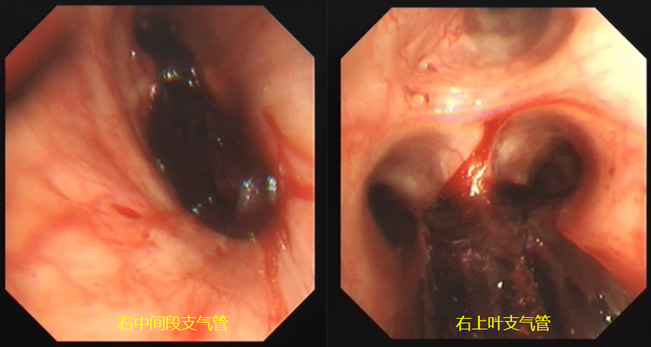

气管镜下可见患者右中间段支气管已被血凝块完全阻塞,右上叶后段和前段大部分也被血凝块阻塞(图3)

图片

图3  气管镜下所见